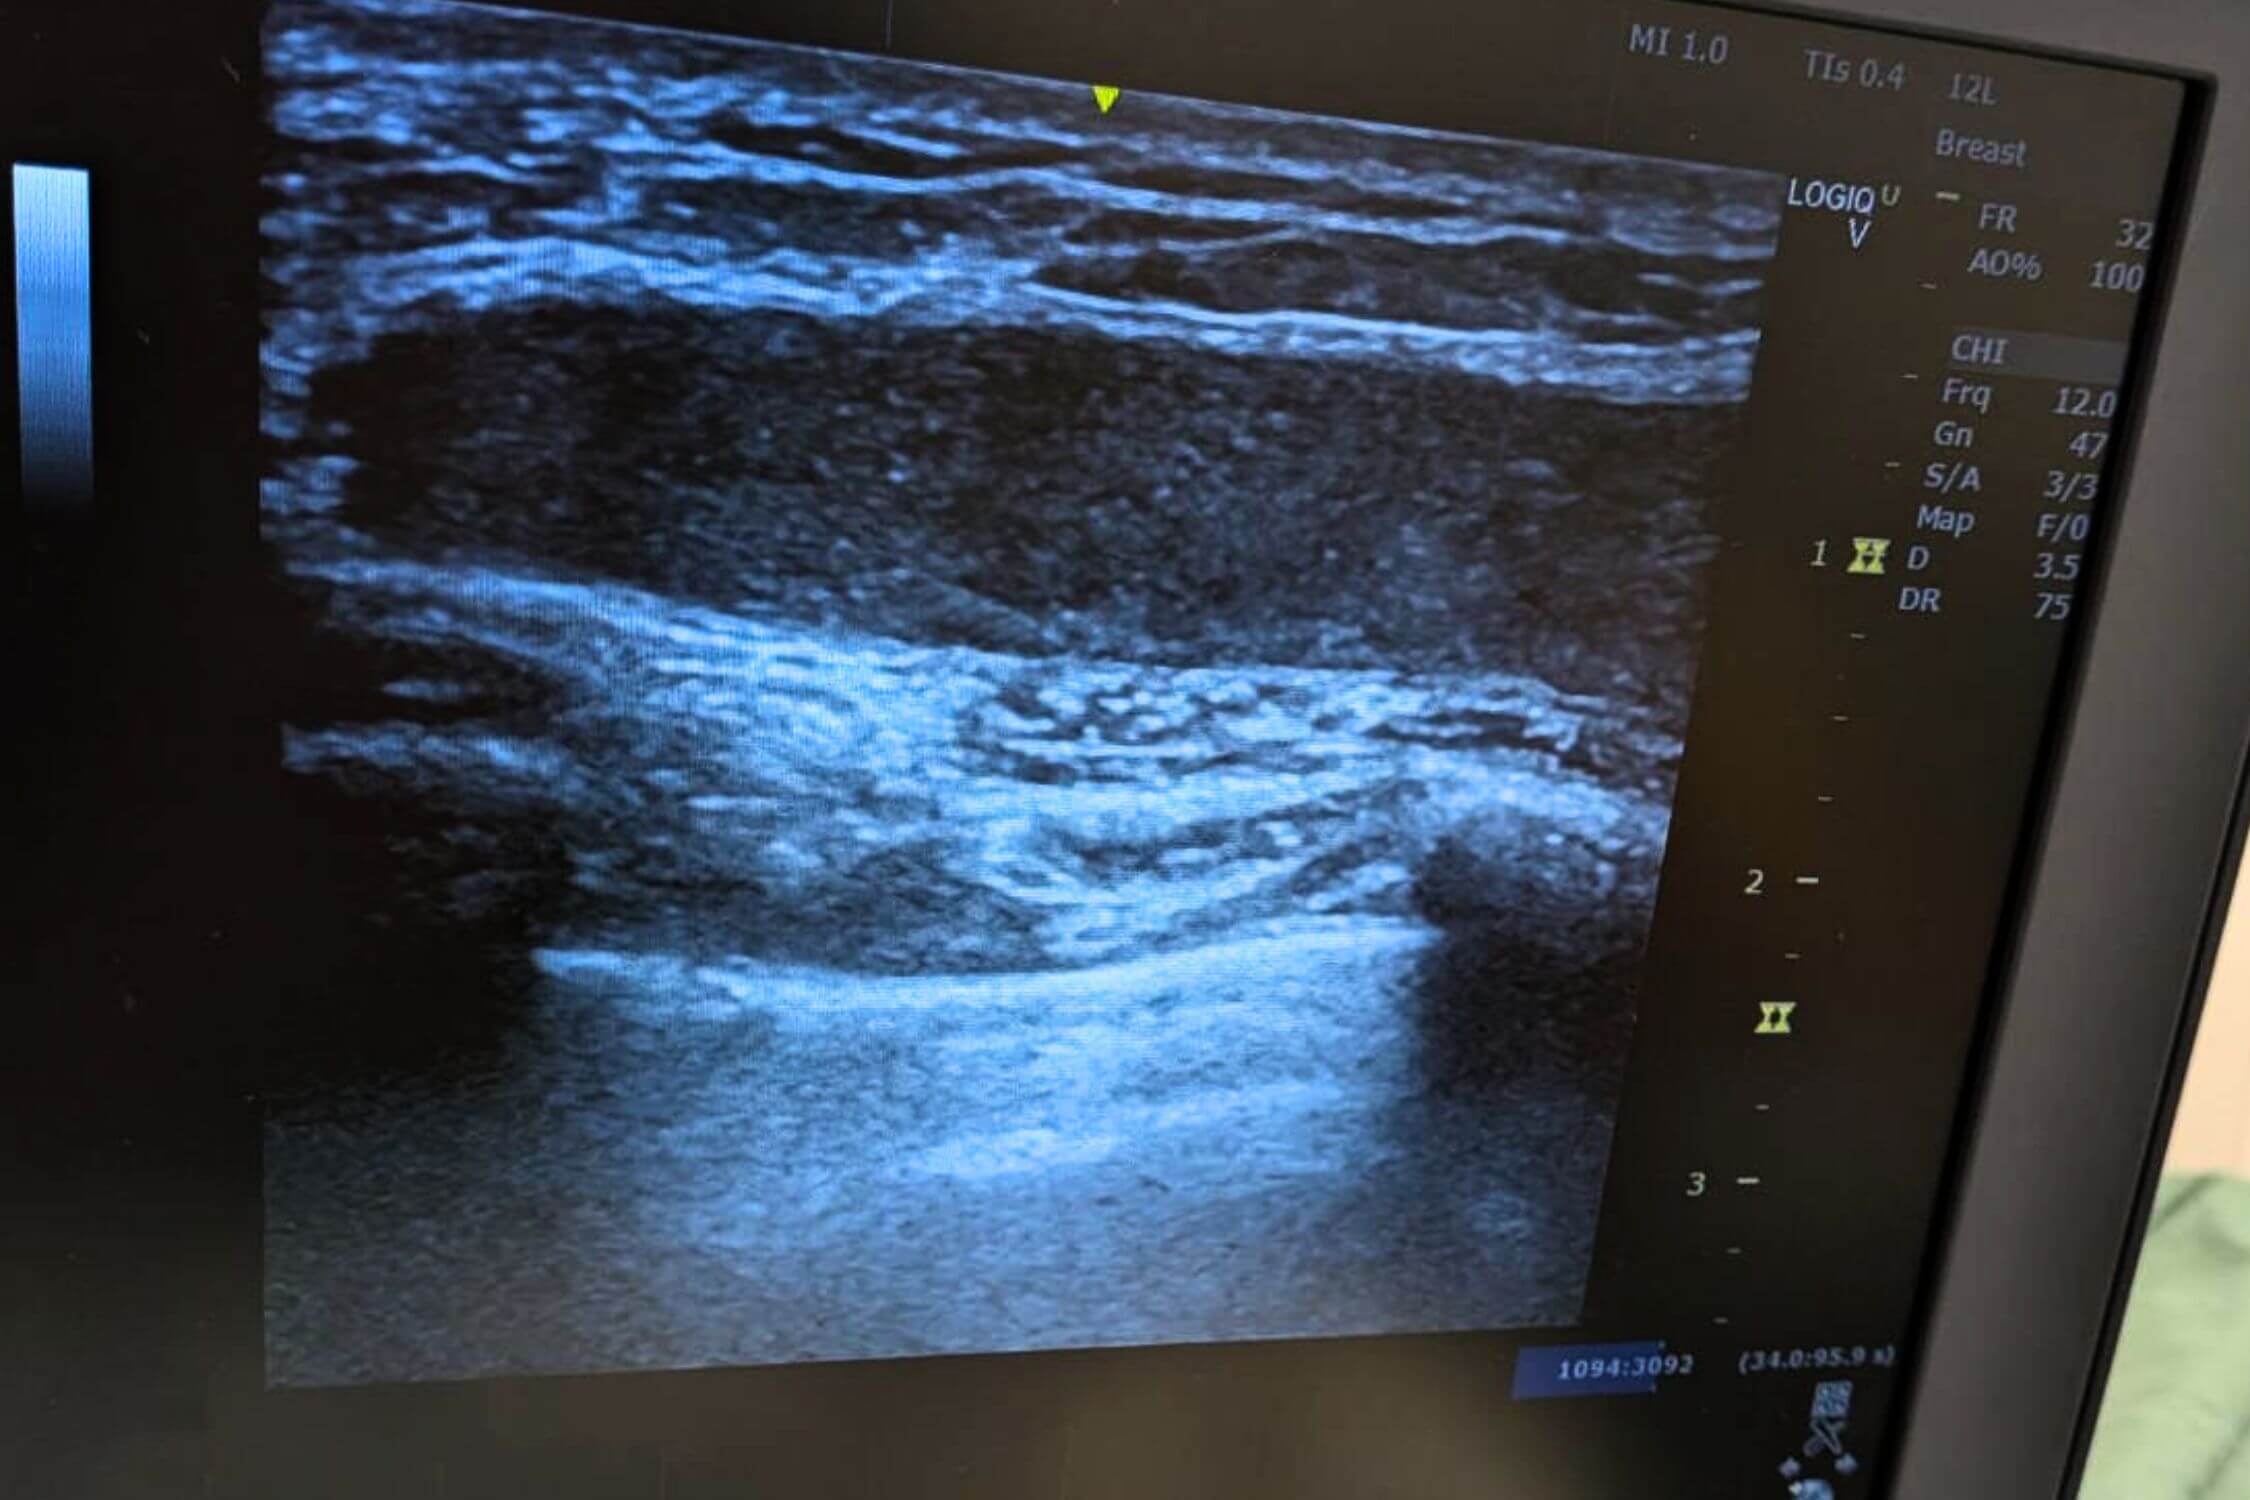

アクアフィリング除去を成功させるためには、製剤がどこに、どの程度広がっているかを術前に正確に把握することです。

当院では高性能なエコー(超音波)機器を駆使し、肉眼では確認できないフィラーの層やしこりの深さをミリ単位で特定します。

吸引前のエコー画像です。黒い溜まりがアクアフィリングです。